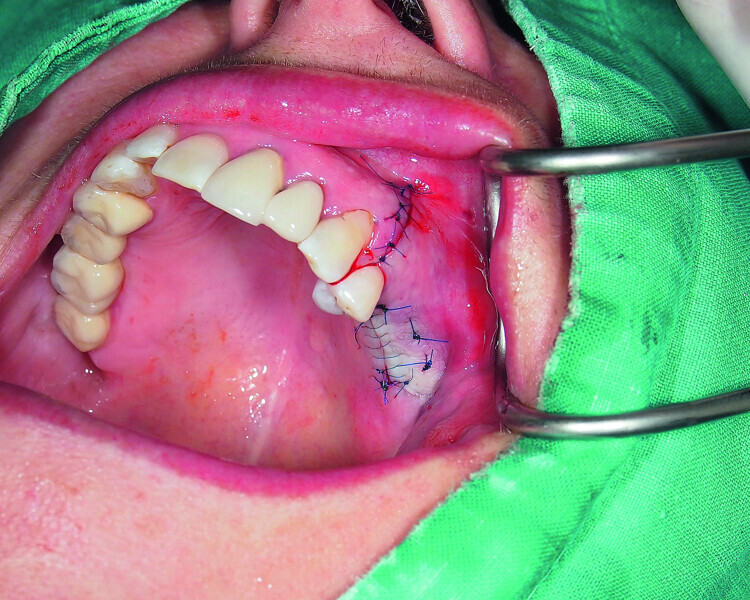

Fig. 20: Wound closure with monofilament sutures.